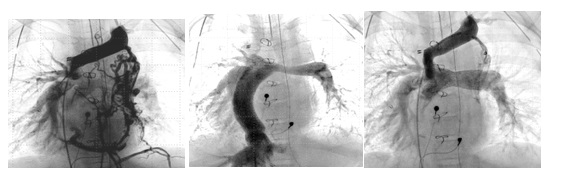

Badania angiograficzne tego samego pacjenta. Wskaż odpowiedni do obrazów opis: